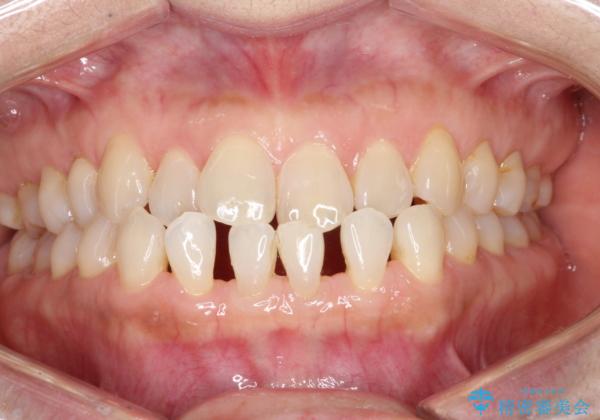

前歯の隙間 インビザラインによる目立たない成人矯正

- 前歯の隙間を気にされて来院されました。

インビザラインにて、目立たずに矯正治療を行うこととしました。

歯と歯の間にある隙間を閉じるのは、インビザラインでもしっかり治療できます。